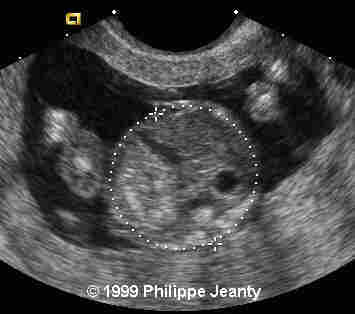

17-year-old primigravida.

This examination is obtained at 18 weeks amenorrhea.

Very few, however, made the most crucial observation: the great disproportion between the head and abdomen. That disproportion is very typical of triploidy (see the lecture on aneuploidy for another example) and I know of no other conditions where such a big difference exist without a concomitant intracranial anomaly such as hydrocephaly, or teratomas… Of course, one of you will come up with a great differential diagnosis and then we will learn even more !

Teaching point: A head much greater than the abdomen is a strong sign of triploidy.

Although commonly encountered in spontaneous abortions, triploidy is rarely seen in fetuses surviving beyond mid-pregnancy. Mid-trimester sonographic findings in three triploid fetuses are described and compared with those reported in six prior cases. While sonographic characteristics are variable, common features include: 1) second trimester-onset fetal growth retardation with a reduced growth potential pattern of anthropometric growth, 2) body asymmetry with relative macrocephaly and an elevated head:abdominal circumference ratio, 3) hydrocephalus, 4) oligohydramnios, and 5) an abnormally large and/or hydropic placenta (in cases of paternal origin). Genetic amniocentesis and amniotic fluid chromosome studies should be performed when ultrasound findings suggestive of fetal triploidy are identified.